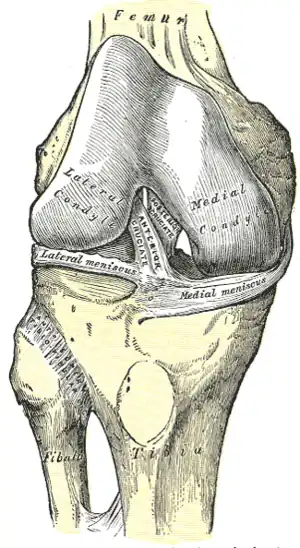

Les deux condyles s'articulent respectivement avec les condyles latéral et médial du fémur pour constituer l'articulation du genou.

L'épiphyse supérieure du tibia est le siège de nombreuses insertions ligamentaires et musculaires intervenant dans l'articulation du genou.

Insertions ligamentaires

- Sur l'éminence intercondylaire s'insèrent les quatre freins méniscaux (antéro-latéral, antéro-médial, postéro-latéral et postéro-médial) , ils permettent de fixer les ménisques de l'articulation du genou.

- Sur les aires intercondylaires antérieure et postérieure on retrouve respectivement le ligament croisé antérieur et le ligament croisé postérieur. Ils empêchent respectivement le tiroir antérieur et le tiroir postérieur.

- Le ligament transverse se situe sur la face antérieure du genou et relie la face antérieure des deux ménisques. Il possède une troisième insertion sur la partie antérieure du plateau tibial.

- Pour renforcer la capsule articulaire du genou on retrouve entre autres le ligament collatéral tibial qui s'insère sur la face médiale de l'épiphyse distale du fémur et sur la face médiale de l'épiphyse proximale. Ce ligament est constitué d'un chef profond qui est lié au ménisque médial et un chef plus superficiel.

Insertions musculaires

- On retrouve sur la face ventrale du tibia, sur la tubérosité tibiale l'insertion distale du muscle quadriceps fémoral via le ligament patellaire.

- Toujours sur la face antérieure les muscles vaste médial et vaste latéral deviennent au niveau de la patella un rétinaculum patellaire respectivement médial et latéral, qui donneront chacun un faisceau direct vers le tubercule sous-jacent et un faisceau croisé vers l'autre tubercule

- Sur la face postérieure on retrouve les insertions des muscles poplité et semi-membraneux.